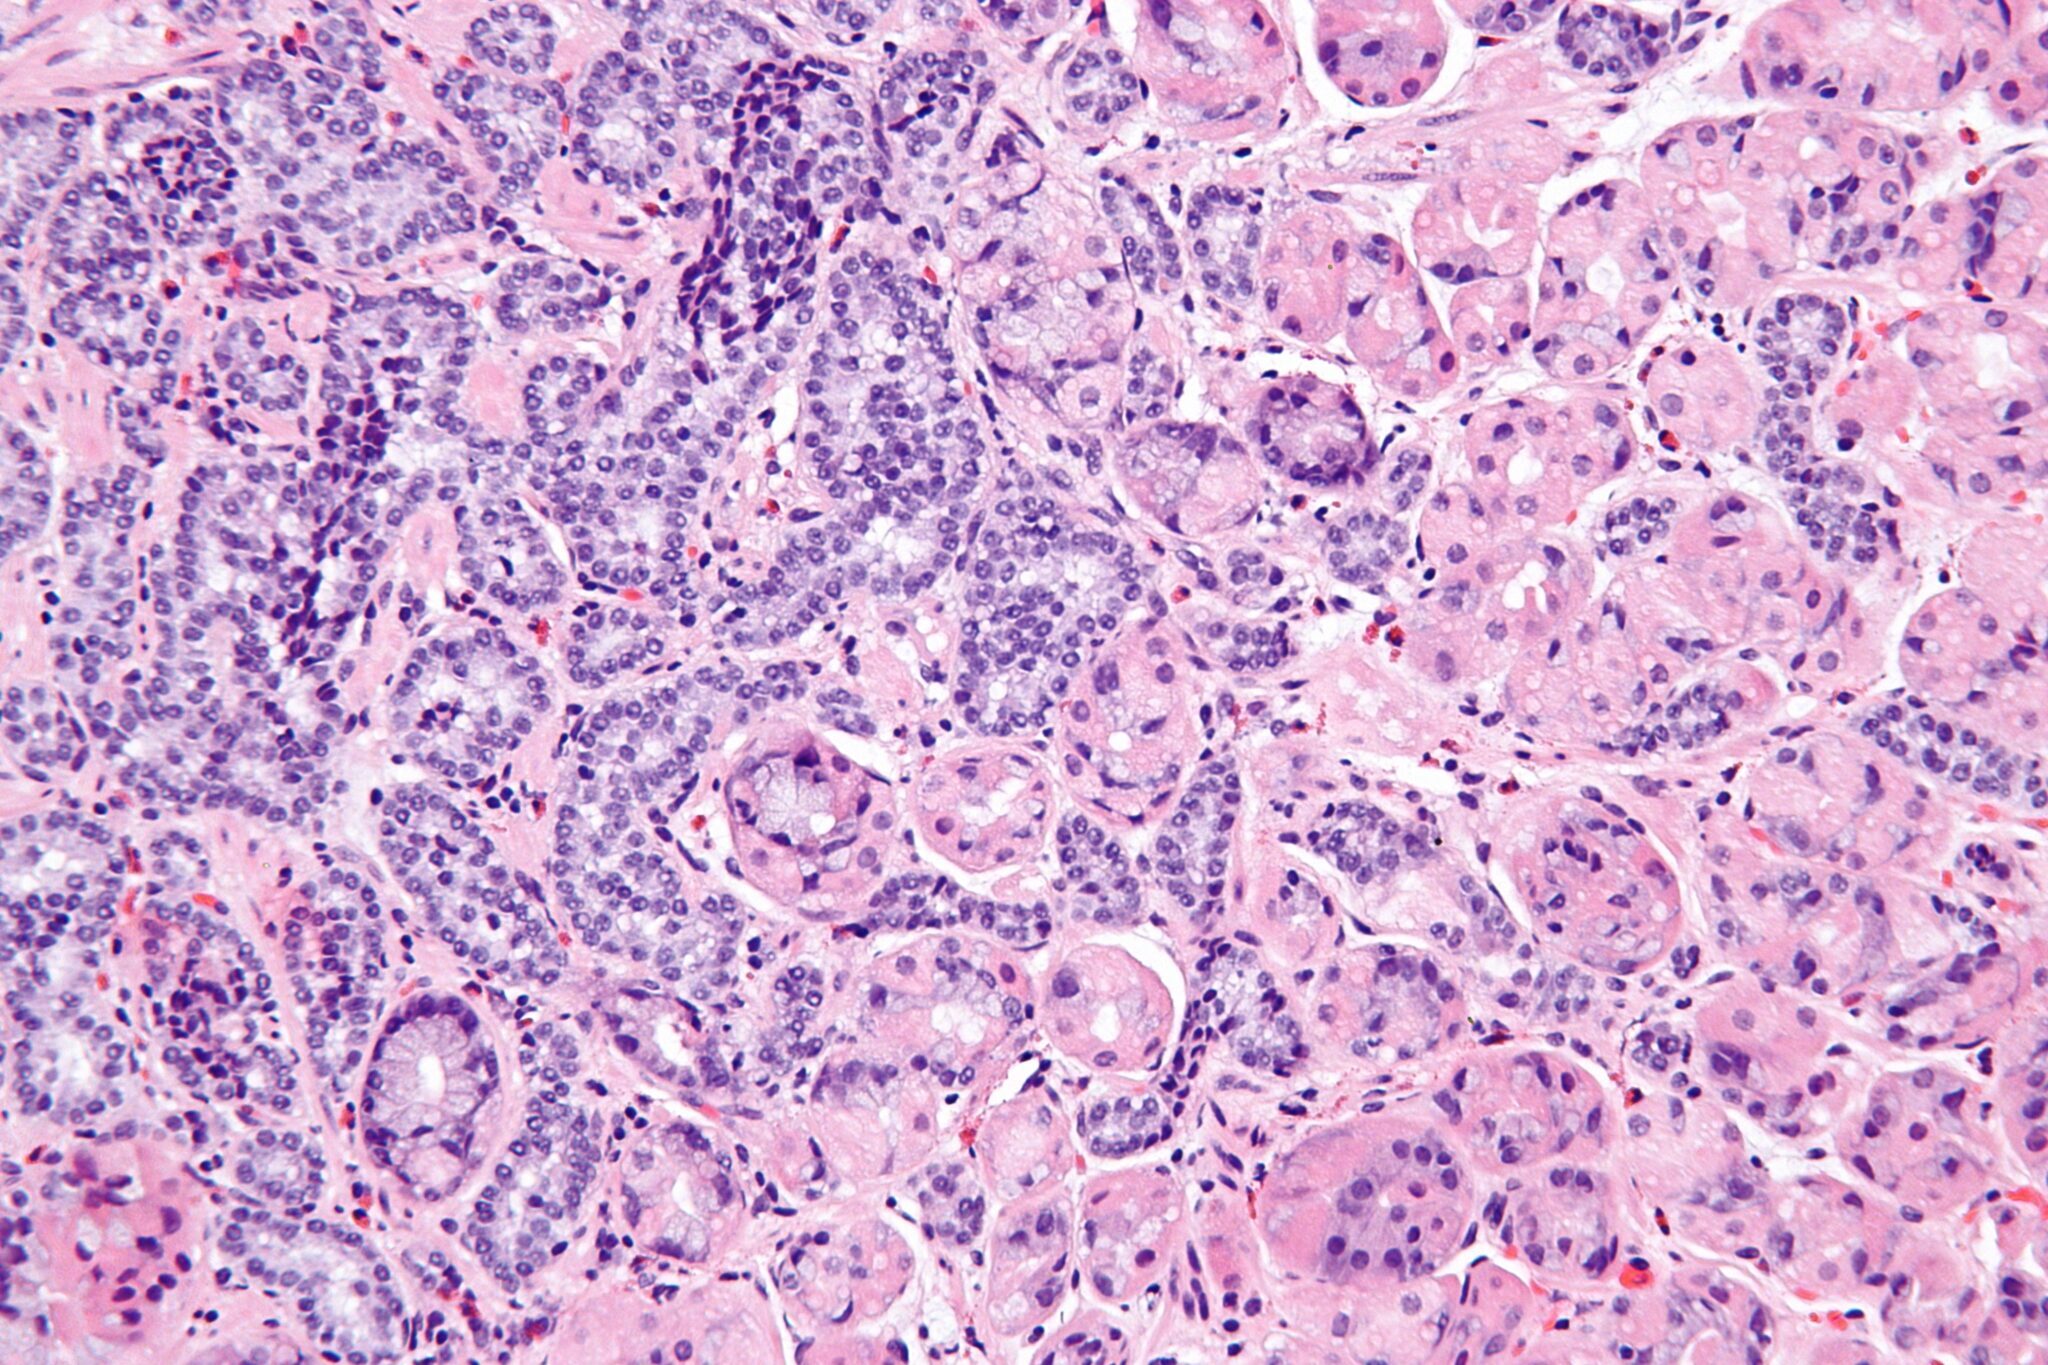

Neuroendocrine Tumors are a diverse group of growths that develop from neuroendocrine cells scattered throughout the body, playing a crucial role in hormonal balance. Such neoplasms could develop in organs like the pancreas, gastrointestinal tract, lung, and other sites with neuroendocrine cells. Neuroendocrine tumors are specified by hormones that they can secrete, thus generating diverse symptoms and complications. Neuroendocrine tumors are relatively rare, though their incidence is increasing with time, presenting varied and challenging diagnostic and therapeutic obstacles because of their heterogeneity & broad clinical spectrums.

Neuroendocrine tumors (NETs) are a diversified group of growths that appear and behave clinically differently. Treatment modalities for Neuroendocrine tumors vary greatly depending on the grade, stage, location, and presence of secreted hormones.

Neuroendocrine tumors are neoplasms originating from the cells of the neuroendocrine system, which produce hormones to regulate various bodily functions.

Their classification is dependent on the site of origin and hormone production.

They include pancreatic NETs, gastrointestinal Neuroendocrine tumors(carcinoids), and lung Neuroendocrine tumors(typical and atypical carcinoids).

Tumor development results from mutation of tumor suppressor genes.